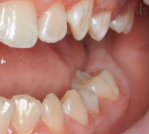

Чистка зубов Air-flow

Доктор: Склярова Владислава Владимировна